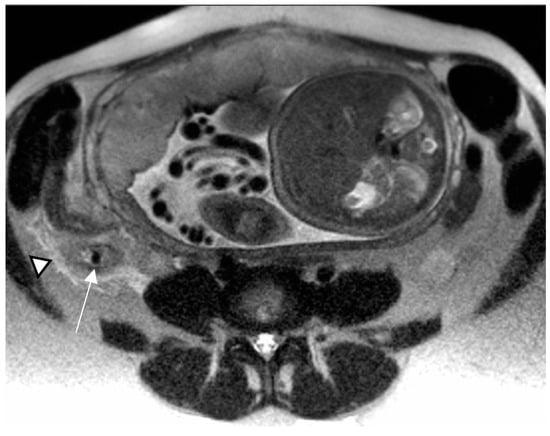

The impaired egress of urine (urinary stasis), due to stones, increases the risk of complications, such as acute pyelonephritis, reported in 1% of pregnancies [80]; in these cases, MRI could be a useful adjunct to clinical diagnosis. The DWI sequence in particular has been found to have increased sensitivity when compared to non-contrast CT (95% and 67%, respectively). The kidney appears enlarged and edematous with areas of lower signal intensity on T2-weighted images and restricted diffusion on DWI (Figure 7).

Figure 7.

Acute pyelonefritis in a 28-year-old woman at 23 weeks of gestation presenting with right-sided abdominal pain and fever. Axial T2WI fat-sat image (a) shows an enlarged right kidney with a dilated pelvis. Axial DWI b-800 (b) clearly depicts wedge-shaped areas of high signal intensity in the right kidney, consistent with the foci of nephritis.

In patients who develop renal abscesses, T2-weighted and DW images respectively show a focal, more hyperintense signal and restricted diffusion, compared to the rest of the parenchyma involved in nephritis [3,54] (Figure 8).

Figure 8.

A 21-year-old woman at 20 weeks of gestation was admitted to the hospital with a diagnosis of pyelonephritis and a temperature of 39.4 °C. Coronal T2-weighted HASTE (a) and axial T2-weighted fat-sat images (b) show a large right-sided and thick-walled fluid collection (arrows), consistent with renal abscess, displacing the kidney.